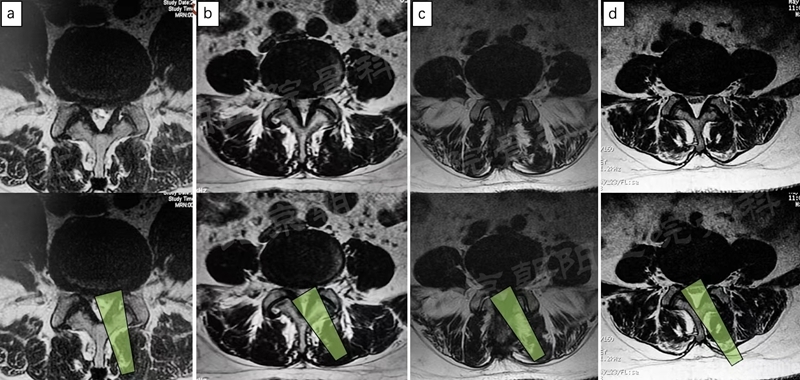

二、 术前定位

通道汇合点1(黄):棘突根部与上位椎体椎板下缘交界处。

优点:软组织较少,方便建立初始空间;解剖标志比较明显,方便辨认。

通道汇合点2(绿):上下椎板交汇处的“V”点。

优点:兼顾显露黄韧带起点和止点;远离椎板间隙,更加安全。

笔者作为初学者,较常选择第二种定位方式。

Tips-1:在对侧椎弓根投影位置临时放置2枚标记针,有助于术者空间定位,防止因长时间操作,或镜下结构辨认不清晰时失去方向,做到对侧,甚至做错节段。